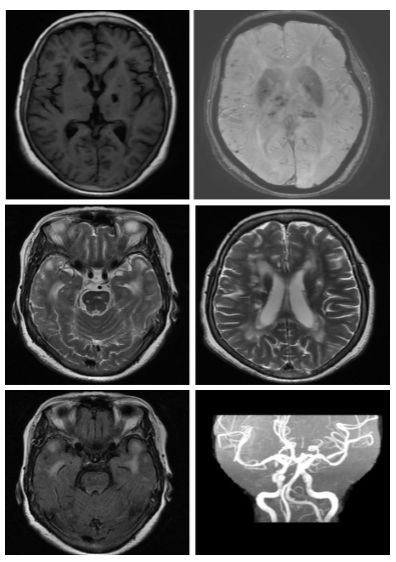

病例7(病例提供: 康健捷 老师)

女,63 岁,反复头晕、四肢乏力、记忆力下降5年。

答案 :伴有皮层下梗死和白质脑病的常染色体显性遗传性脑动脉病(CADASIL)

本病例比较典型,绝大多数老师回答正确。CADASIL主要累及侧脑室周围和深部白质。以额叶白质最常受累,其次为颞叶和顶叶,而枕叶受损程度相对较轻。外囊、颞极的对称性异常信号对诊断有高度提示作用。胼胝体亦可全层受累,引起胼胝体萎缩。当然也有不典型CADASIL,表现为脑小血管病,如微出血、脑萎缩等。可以通过ADASIL量表进行筛查,如果总分≥15分者,提示CADASIL。